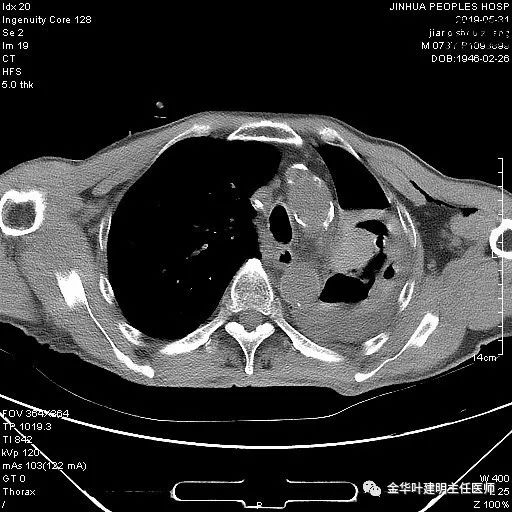

考虑左侧大量胸腔积液,遂进一步胸部CT检查:

以上是肺窗表现,下面为纵隔窗影像: